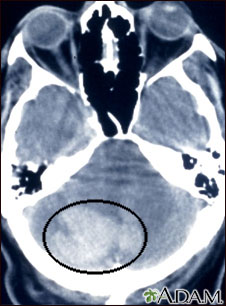

Intracerebellar hemorrhage shown by CT scan. This hemorrhage followed use of t-PA.